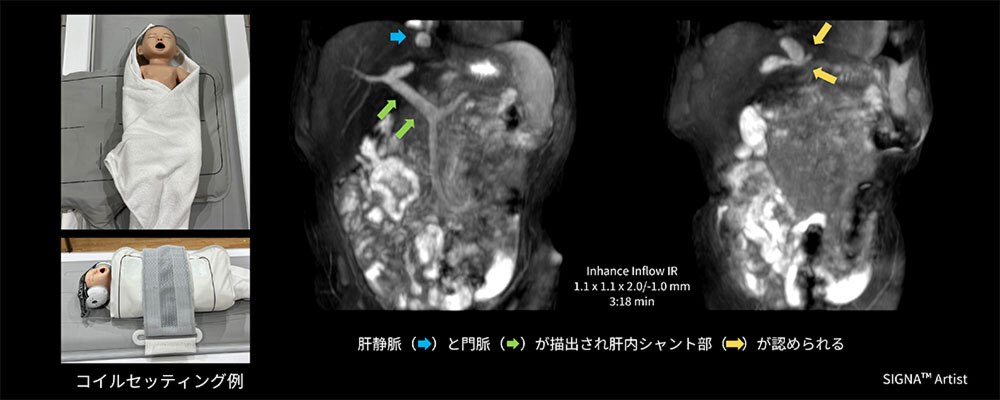

Case4 新生児の門脈肝静脈シャント非造影検査

生後6か月の乳児。超音波検査時にて体循環門脈シャントを指摘されており、複数シャントの有無、血管腫の有無についてMRI検査を実施。ポジショニング時にGEM Flex Coilの使用を検討したが、体動や患児の固定及びコイルの固定が懸念されたため、MP Coil を使用し検査を施行。

AIR™ Coilsに使用シーケンスの制限はないため、Inhance Inflow IRで検査を実施。門脈P3と左肝静脈間にシャント形成を認め、その他シャント形成は認められなかった(図6)。

結果として患児の体型に合わせてコイルをフィットさせることができ、ポジショニングも簡便かつスムーズに行うことができた結果、追加鎮静もなく迅速な検査実施に貢献できた一例。

図6 新生児の門脈肝静脈シャント非造影検査におけるMP Coilのセッティング例と臨床画像